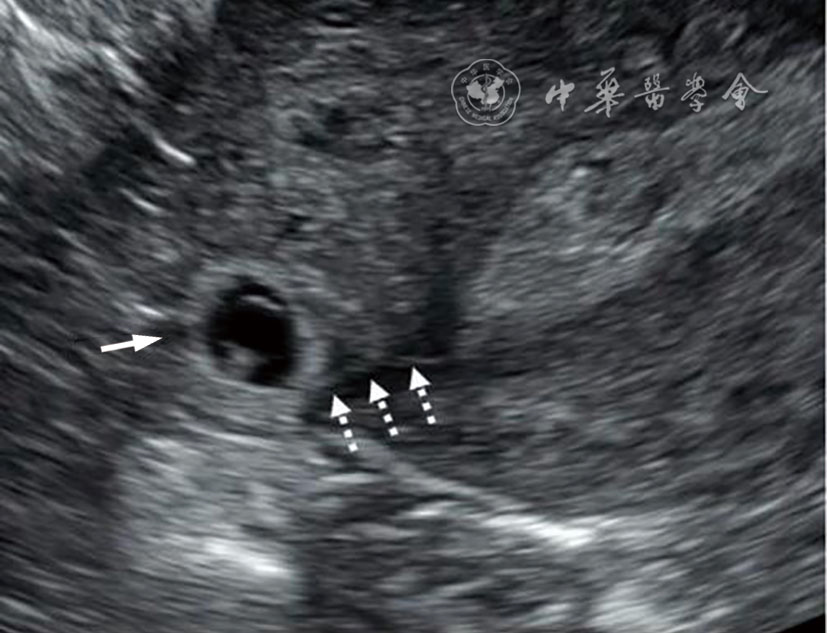

2.输卵管间质部异位妊娠:输卵管间质部异位妊娠较罕见,指受精卵着床于输卵管间质部(嵌入子宫肌壁内的输卵管近端部分)(图4)。超声诊断要点包括:(1)子宫与妊娠囊间滑动征阴性;(2)三维冠状切面重建图像显示子宫肌层部分包绕妊娠囊(妊娠囊周边子宫肌层组织呈“爪形征”),或子宫内膜与妊娠囊间可见薄层肌层组织;(3)间质线征仅偶见(图5),但该征象诊断输卵管间质部异位妊娠特异度较高。应避免使用‘宫角妊娠’或‘宫角异位妊娠’。

图4 输卵管间质部异位妊娠超声图像。图a为经阴道超声横切面灰阶图像,图b为三维超声冠状面重建图像。29岁孕妇(孕5周3天)的妊娠囊(测量游标)与子宫内膜(*)之间存在肌层组织(实线箭头),肌层组织的“爪形征”(虚线箭头)证实妊娠着床于输卵管间质部,提示为输卵管间质部异位妊娠。应避免使用‘宫角妊娠’或‘宫角异位妊娠’。三维超声冠状面重建可更清晰显示妊娠囊与子宫内膜分离,符合输卵管间质部异位妊娠(图4译自参考文献[1])

图5 间质线征超声图像。图为33岁孕妇(孕6周0天)经阴道超声横切面灰阶图像,显示右侧输卵管间质部异位妊娠(实线箭头)。除输卵管间质部异位妊娠特征性超声表现外,另可见一纤细高回声线(虚线箭头)连接子宫内膜与异位妊娠囊,为“间质线征”(图5译自参考文献[1])